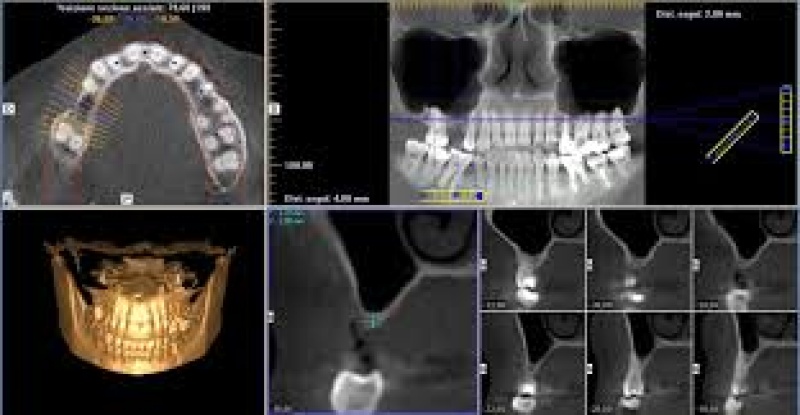

TAC 3D CONE BEAM